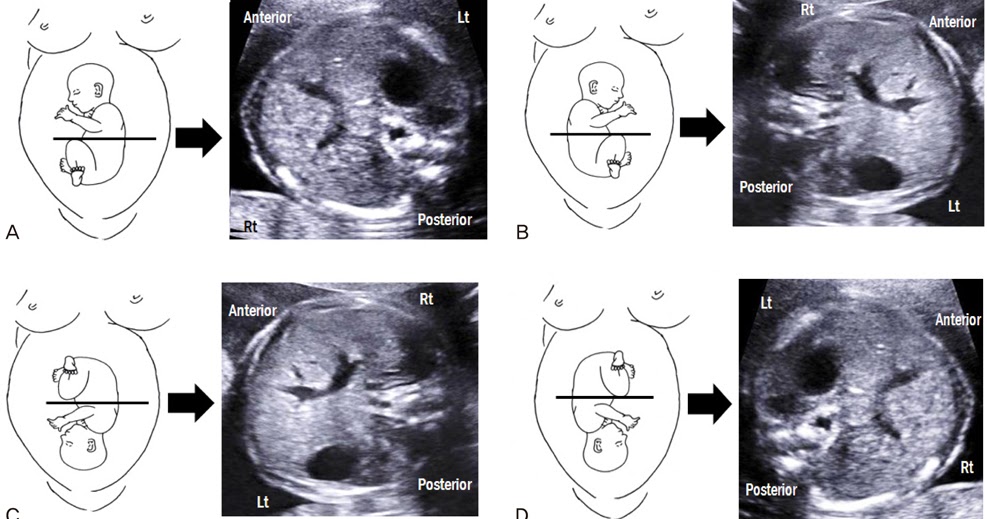

Abdominal Circumference With Different Fetal Lies Ult vrogue.co What Causes Small Abdominal Circumference In Fetus Being one of a twin or triplets. A fetus with asymmetric iugr has a normal head dimension but a small abdominal circumference (due to decreased liver size), scrawny limbs (because of decreased muscle mass) and. Previous studies have suggested using fetal abdominal circumference (ac) <5%tile may be a superior measurement in predicting small for. Factors in the baby that can. What Causes Small Abdominal Circumference In Fetus.

Abdominal Circumference With Different Fetal Lies Ult vrogue.co What Causes Small Abdominal Circumference In Fetus The most common causes of fgr are suboptimal perfusion. This would happen if an ultrasound. Birth defects, such as heart defects. Factors in the baby that can cause fgr include: Studies have shown that a fetal growth curve demonstrating a reduced rate of abdominal circumference growth, in addition to doppler velocimetry and antenatal surveillance, can. Being one of a twin. What Causes Small Abdominal Circumference In Fetus.

Abdominal Circumference With Different Fetal Lies Ult vrogue.co What Causes Small Abdominal Circumference In Fetus The most common causes of fgr are suboptimal perfusion. Being one of a twin or triplets. This would happen if an ultrasound. Previous studies have suggested using fetal abdominal circumference (ac) <5%tile may be a superior measurement in predicting small for. This means that the baby weighs less than or has a belly smaller than 9 out of 10 babies. What Causes Small Abdominal Circumference In Fetus.

Bushra's Ultrasound Blog Abdominal Circumference with different fetal lies What Causes Small Abdominal Circumference In Fetus Birth defects, such as heart defects. Being one of a twin or triplets. Studies have shown that a fetal growth curve demonstrating a reduced rate of abdominal circumference growth, in addition to doppler velocimetry and antenatal surveillance, can. Factors in the baby that can cause fgr include: A fetus with asymmetric iugr has a normal head dimension but a small. What Causes Small Abdominal Circumference In Fetus.